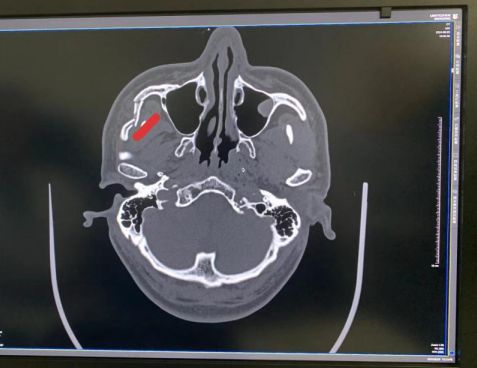

男子被砸致面部破碎 口腔专家巧手精雕重塑容颜